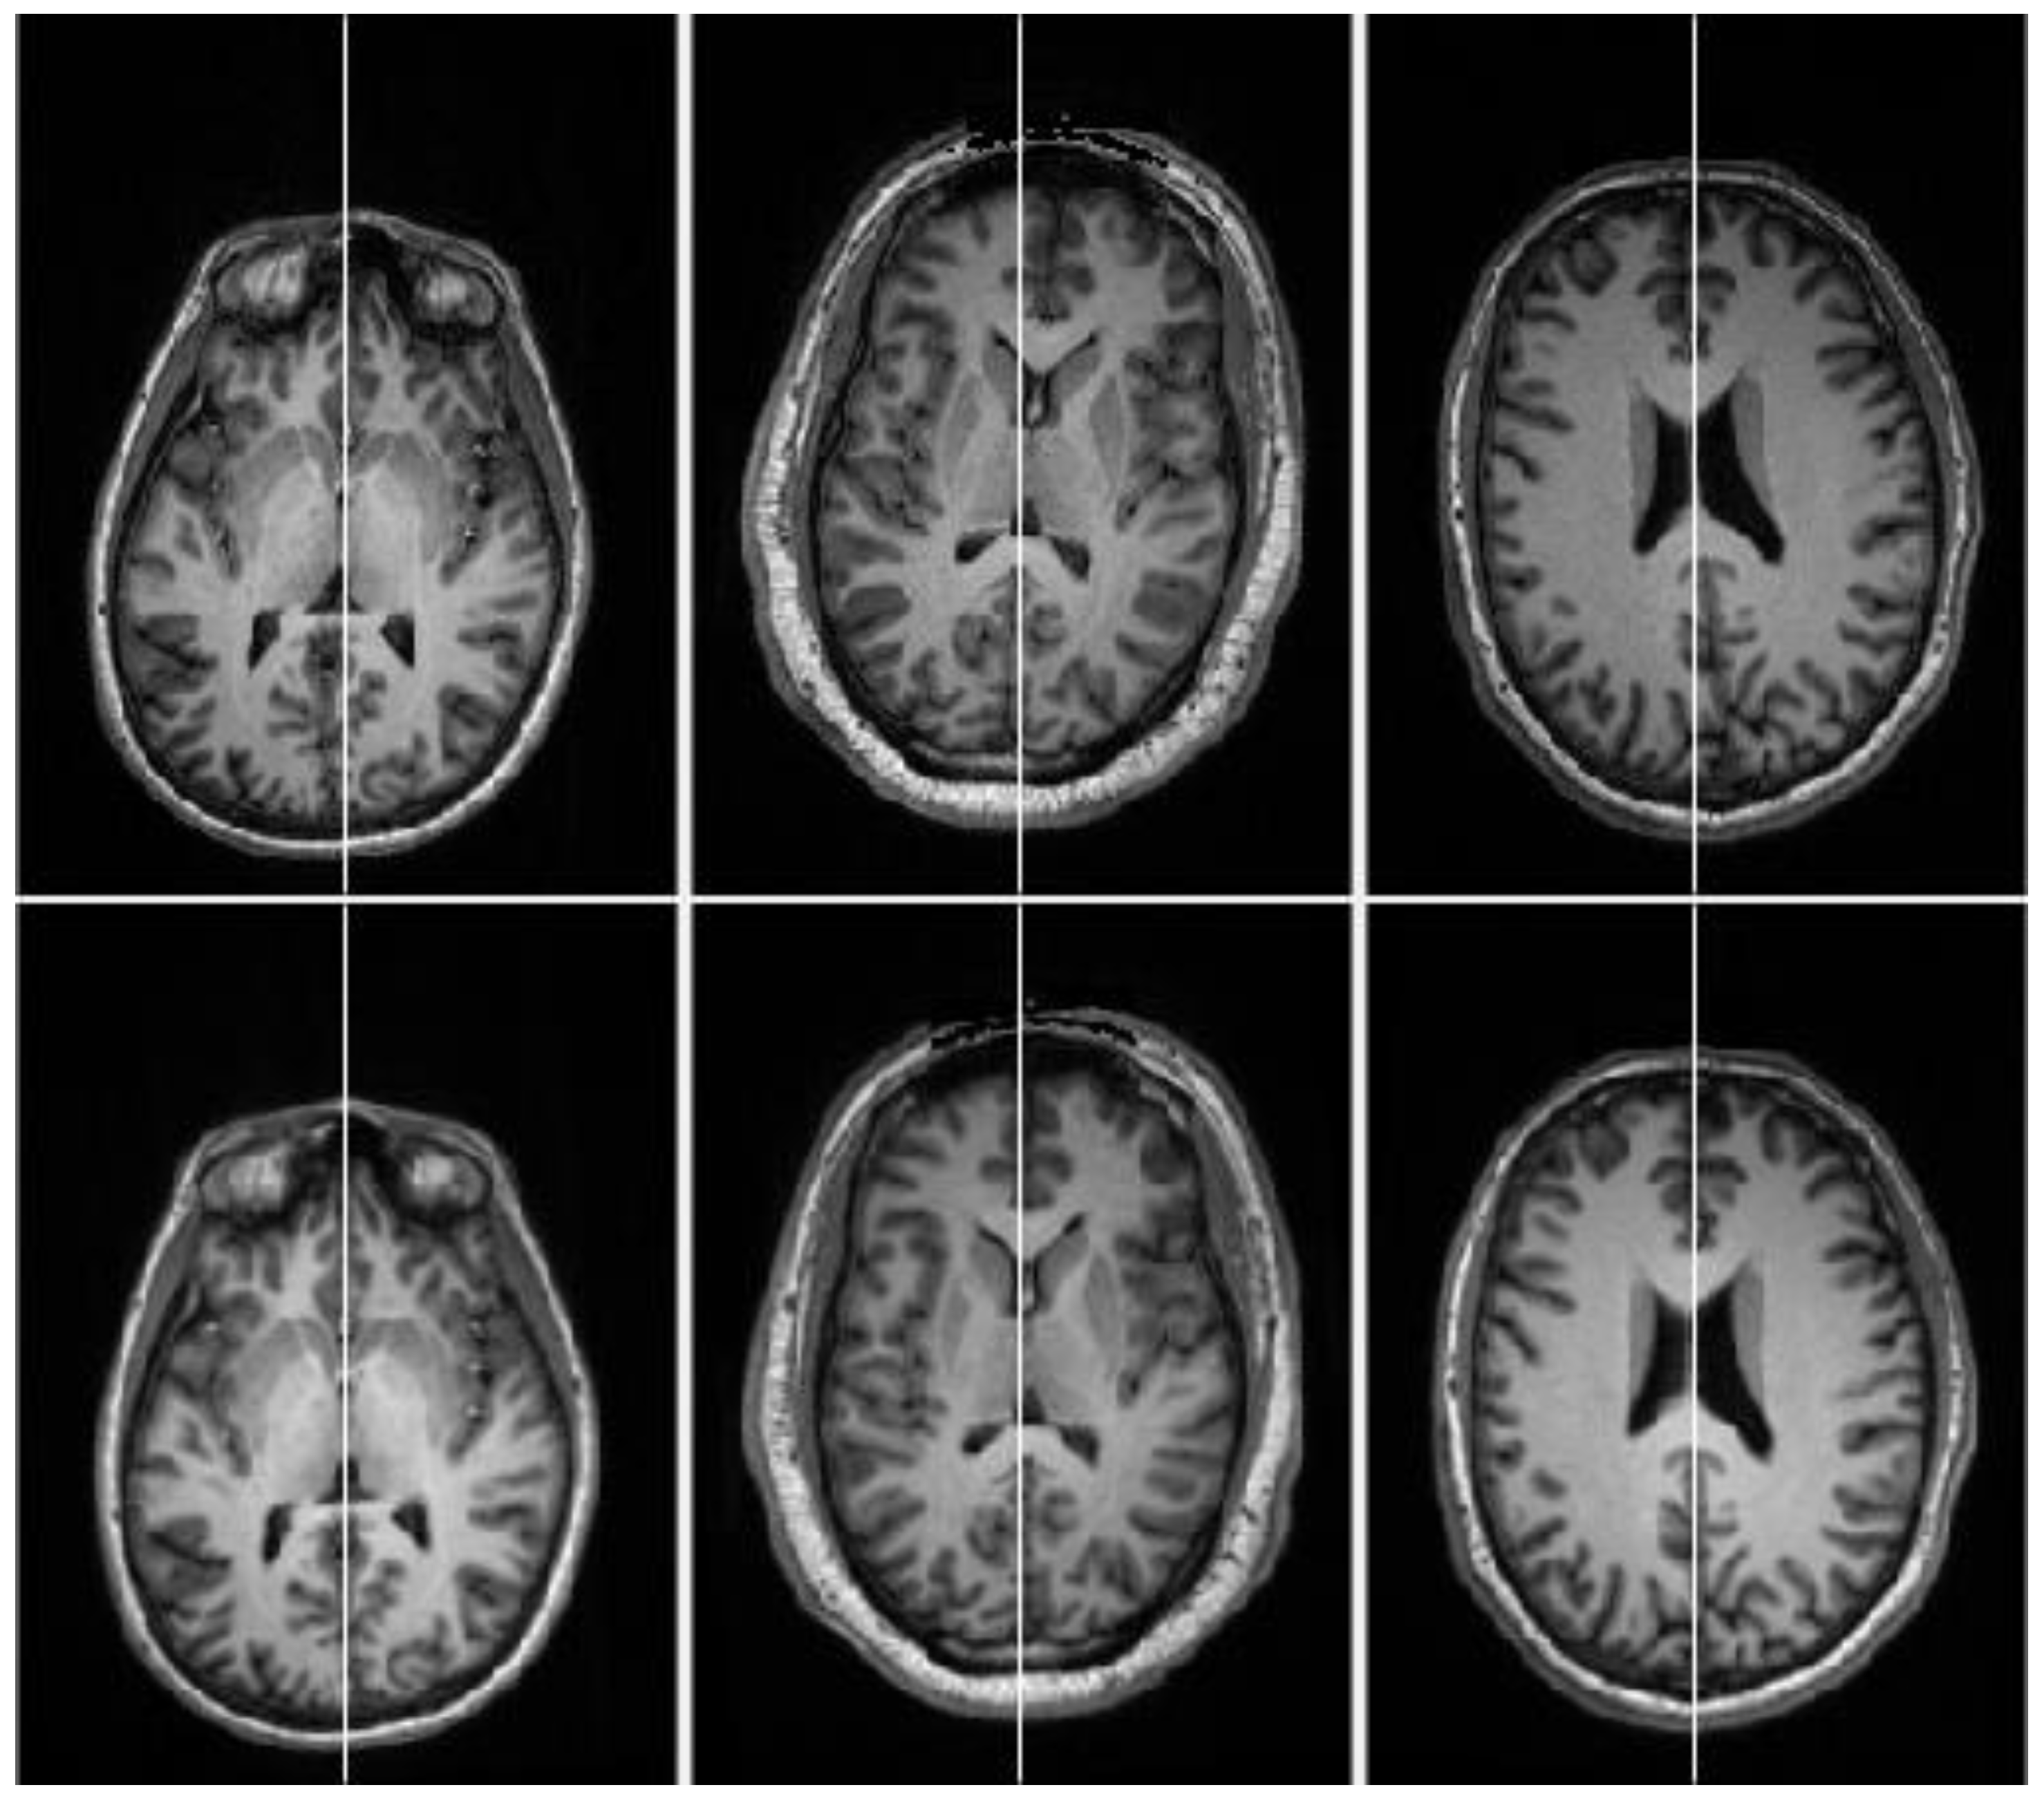

3. Results and Discussion

3.2. Evaluation and Comparison on Synthetic Datasets

3.3. Evaluation and Comparison on Real Datasets